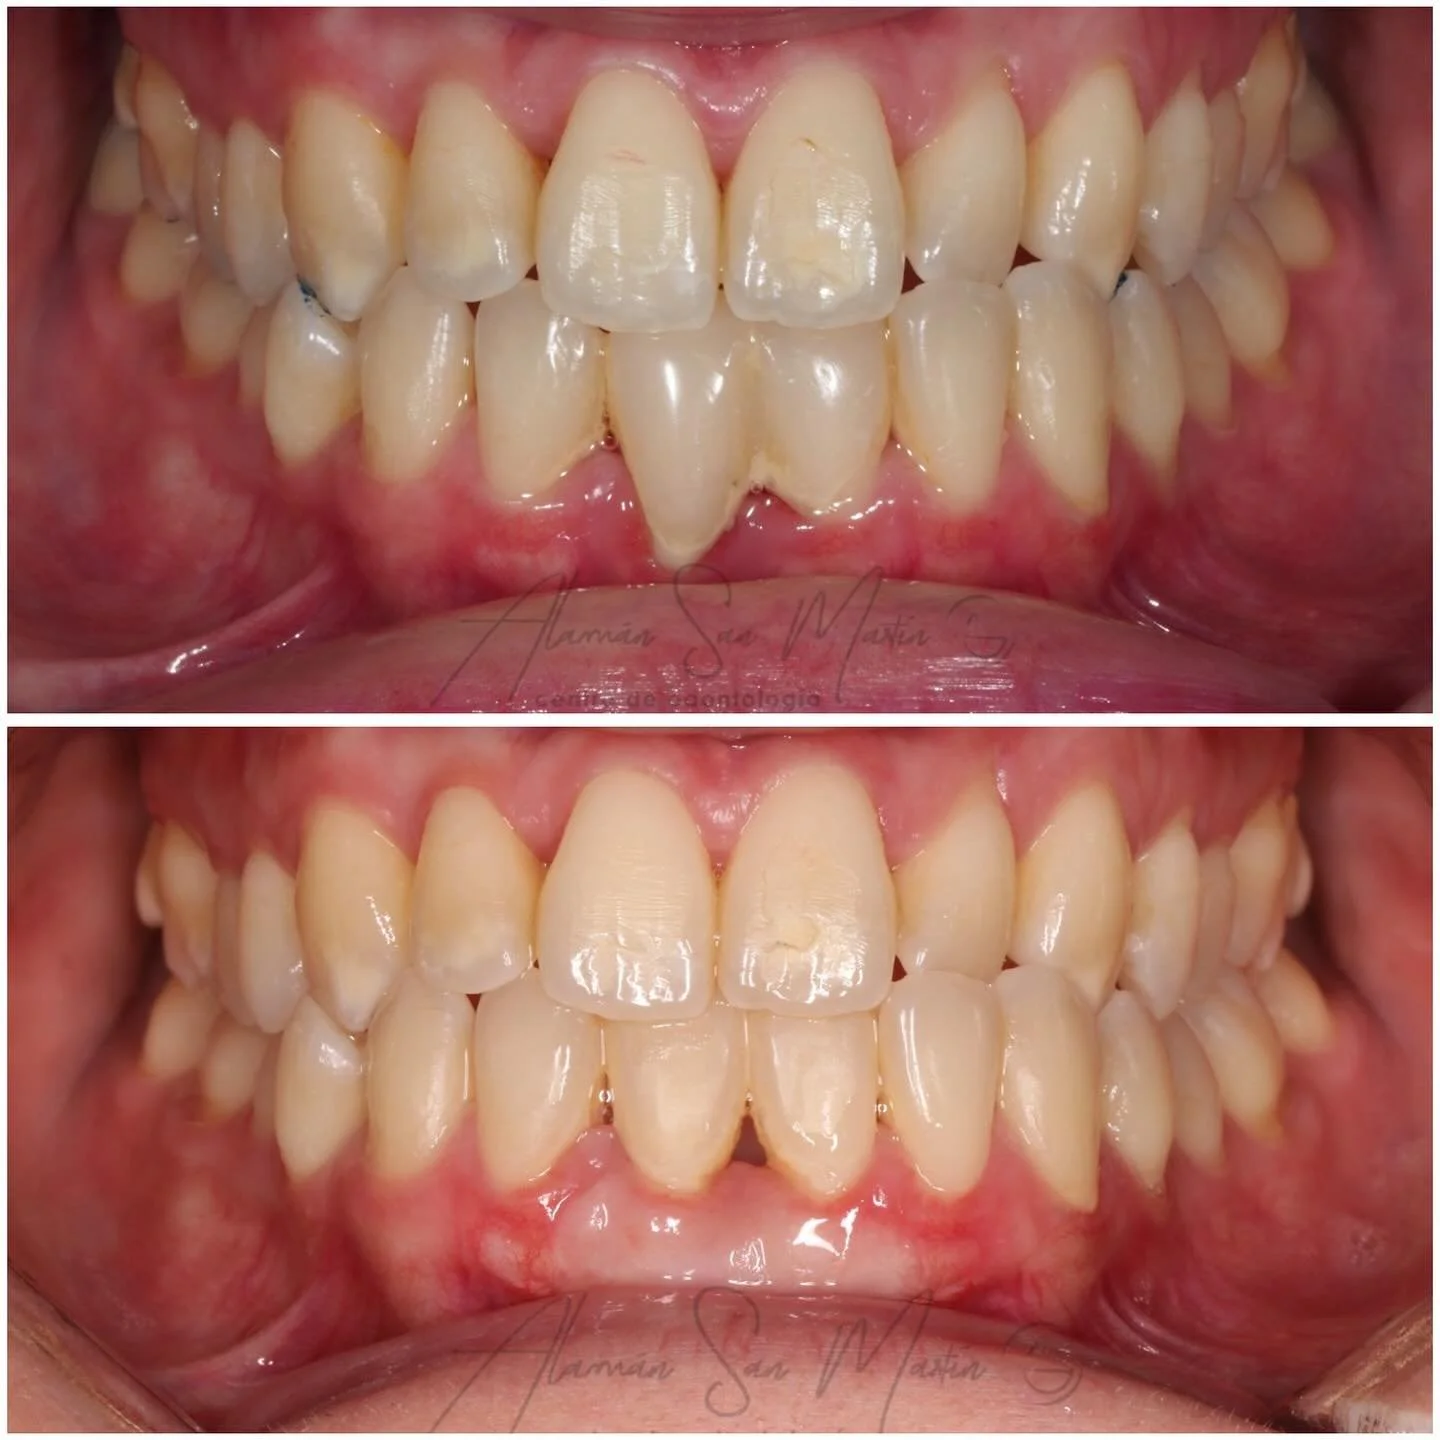

En la Clínica Alamán San Martín todos los tratamientos de Ortodoncia los realiza un Especialista Universitario en Ortodoncia, siempre tras un estudio diagnóstico en profundidad con la exploración clínica y valoración de todos los registros necesarios según la complejidad de cada paciente.

Actualmente la Ortodoncia se realiza a cualquier edad para mejorar la salud bucal, la función masticatoria y la estética, al conseguir un buen alineamiento de los dientes y una relación ósea intermaxilar adecuada con una oclusión normal, por lo que recomendamos hacer una revisión de ortodoncia por lo menos desde los 6 años de edad si no se detecta nada antes.

En Clínica Alamán San Martín ofrecemos diversos tratamientos de ortodoncia como: Ortodoncia infantil y adultos, Ortodoncia Estética, Ortodoncia Transparente con Alineadores, y Ortodoncia quirúrgica para Cirugía ortognática.